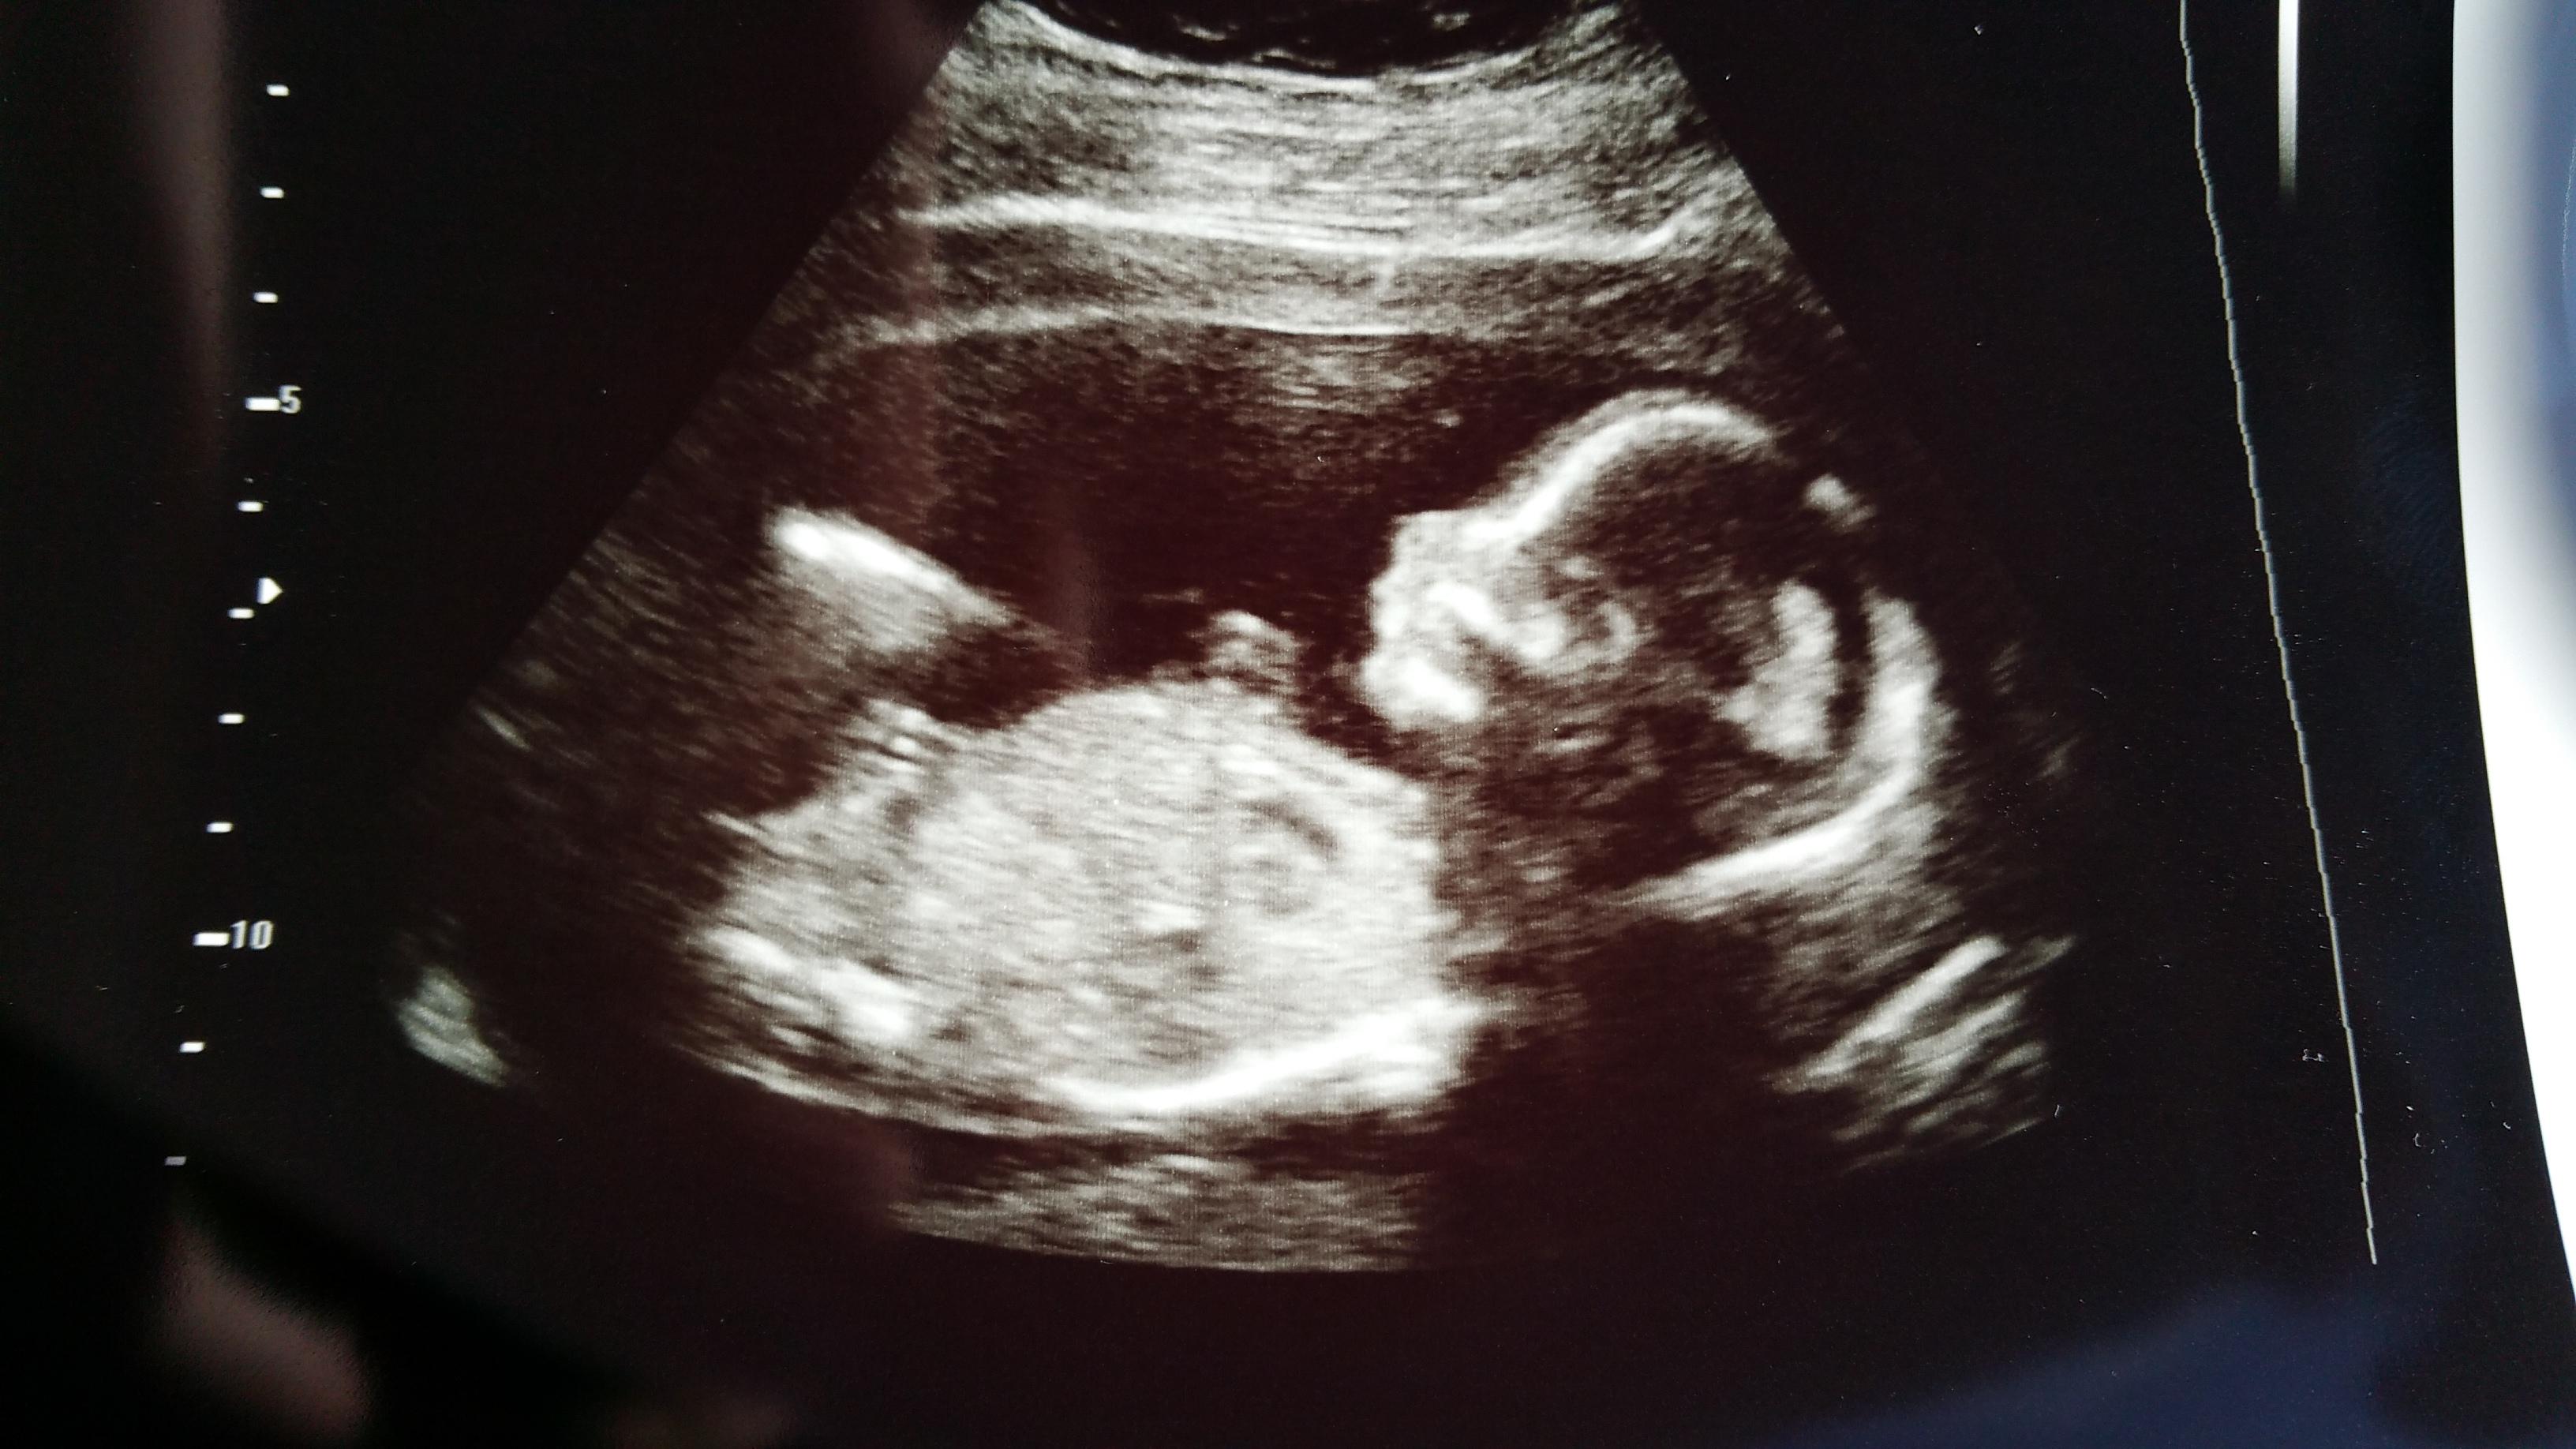

I love the 20-week scan! Baby clearly looks like a real baby and still all fits on the screen. We are team green, but baby's legs were crossed anyway (you can see the feet together at the top left). The tech also said he/she had its boxing gloves on because its hands were up by its face, but every once in a while the face would poke out. So much fun and super cute!